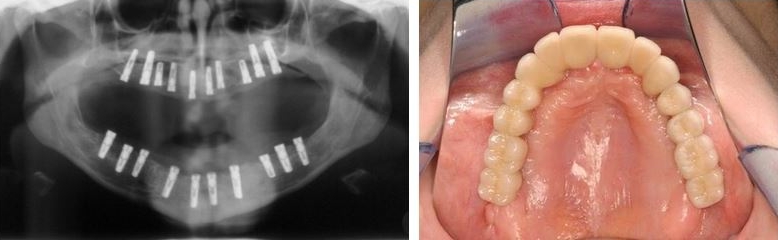

- Zahnimplantate Burgenland Eisenstadt Mattersburg Zahnkaiser . Festsitzender Zahnersatz, Wo Die Zahnkronen, Zahnbrückenglieder Oder Rundbrücke Auf Eine Bestimmte Anzahl Von Zahnimplantaten Fest Zementiert Oder Geschraubt Werden.

- All On 4 Zahnersatz Bei Vollstandigem Zahnverlust : Schablonengeführte Operation, Setzen Der Implantate, Abdrucknahme Und Eingliederung Der Therapeutischen Brücke (Noch Am Gleichen Tag).